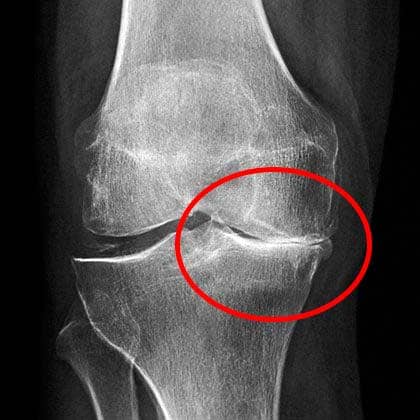

Izgled mog koljena u tom trenutku: jaka, nepodnošljiva bol.

Nakon pregleda, liječnica je dugo gledala rendgenske snimke i rekla mi da prestanem s bilo kakvim teškim fizičkim radom. Rekla mi je da ne podižem ništa teže od 2 kg.

Rendgenske snimke pokazale su velik problem u koljenu.